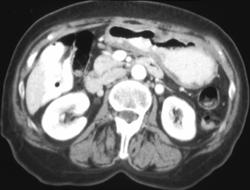

Gastric Cancer